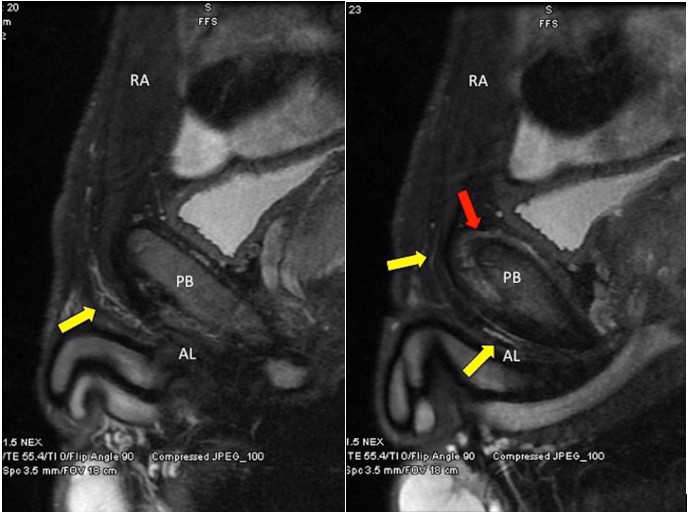

L’imagerie par résonance magnétique (IRM) est la modalité la plus sensible et spécifique permettant d’identifier avec précision les différentes lésions pouvant être observées dans ce contexte clinique (2,11) (figure 1).

Figure 1 : IRM pelvien en T2 montre une augmentation de l’intensité du signal au niveau de l’aponévrose commune des muscles rectus abdominis et adductor longus. La flèche jaune indique une lésion au niveau de l’aponévrose (à gauche) et ue augmentation de l’intensité du signal le long des tendons des 2 muscles (à droite).